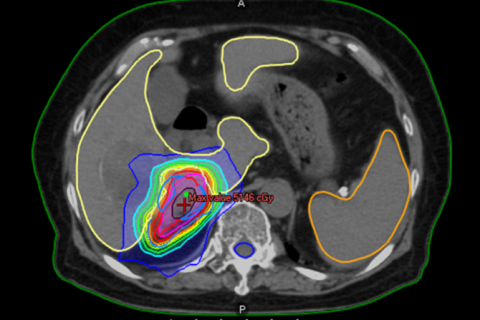

腎臓がんに対する定位照射

少数個転移(オリゴ転移)に対する定位放射線治療(ピンポイント照射)について

がんが他の部位に転移している場合でも、転移の数が限られている状態を「少数個転移(オリゴ転移)」と呼びます。 このような状態では、転移した病変一つひとつを狙って治療することで、病状の進行を抑えることが期待できる場合があります。

少数個転移に対する治療法の一つが、定位放射線治療(ピンポイント照射)です。

定位放射線治療は、病変の位置を正確に捉え、周囲の正常な組織への影響をできるだけ抑えながら、狙った部位に集中的に放射線を照射する高精度な治療法です。

当院では、少数個転移に対する定位放射線治療を、4回から20回に分けて行っています。

転移の部位や、周囲に副作用が起こりやすい臓器が近い場合には、照射回数を増やして1回あたりの放射線量を抑え、安全性を高める工夫を行っています。